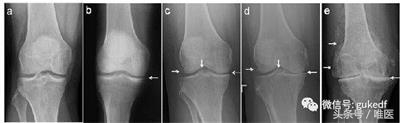

经常会遇到有人发现自己“关节疼、肿”,到医院拍片,诊断为“滑膜炎”(图1a,1b)、“骨质增生”(图1c,1d,1e),还有诊断为“关节炎”的(图1d,1e)。那到底是哪种病?我们对这几种病名分别了解一下。

图1.膝关节的各种X线拍片表现

从上可见,关节软骨磨损、骨关节炎就会继发滑膜炎。因为在常规X线片上无法观察到明显的关节周围骨质增生(骨赘、骨刺形成),或关节间隙变窄(图1c,1d,1e),因此被称之为“滑膜炎”。

患者关节肿痛,拍片子后看到报告单上描述的“骨质增生”,同时观察到X线片上关节(股骨或胫骨)周缘或髁间棘处增生的骨质(图1c,1d,1e左侧和中间白箭头),就断定自己得了“骨质增生”(有了“骨刺”)。

从前面我们能够知道,过度活动或年龄增大会造成关节磨损。轻度的关节损伤会造成“滑膜炎”;重度的关节损伤或年龄增大造成关节磨损会导致“退行性骨关节炎”,也就是常说的“关节炎”(图1c,1d,1e)。